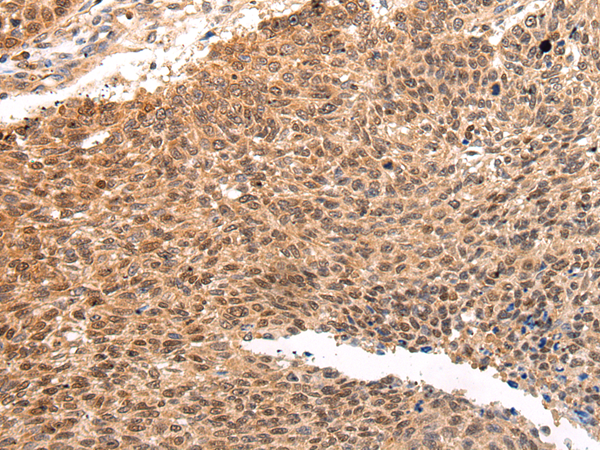

IHC positive control: |

Human lung cancer and human thyroid cancer |

IHC Recommend dilution: |

25-100 |